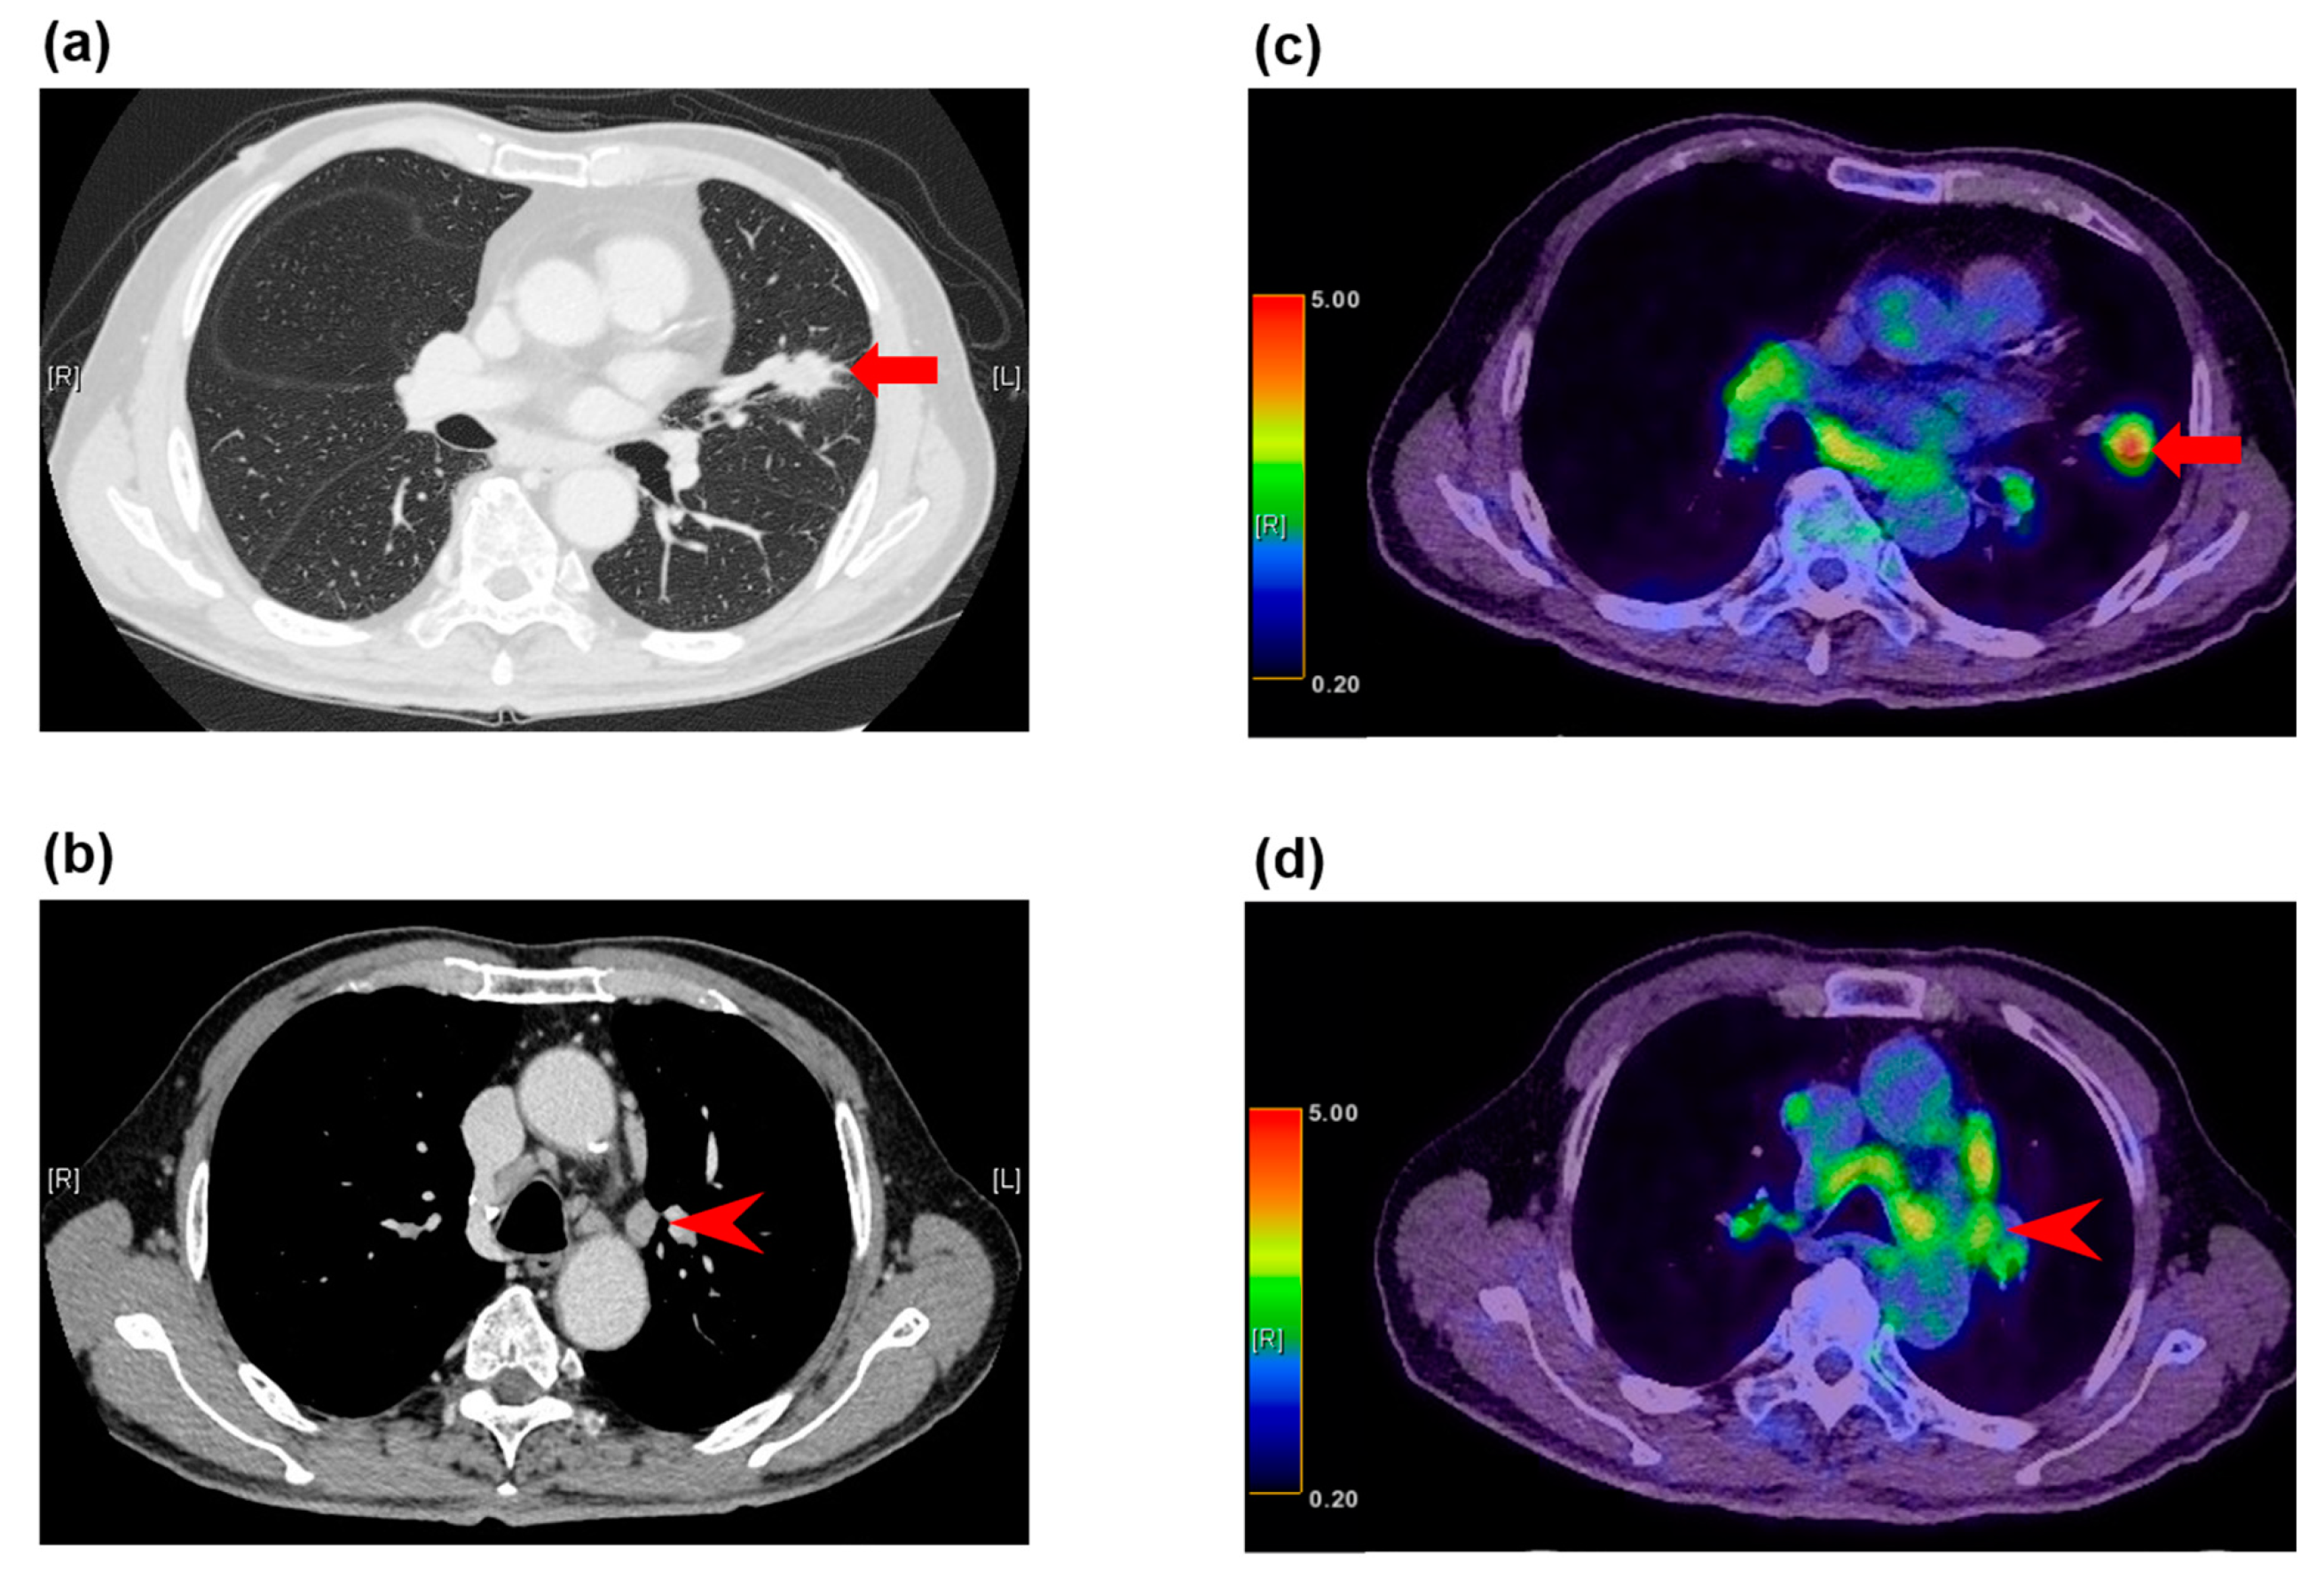

Figure 2.

False positive FDG-PET/CT findings in enlarged lymph nodes in a 78-year-old man with squamous cell carcinoma. (a) The CT image shows a left upper lobe tumor (arrow), (b) and enlarged station 5 lymph nodes (arrowhead). (c) The FDG-PET/CT image shows FDG accumulation with a maximum SUV of 6.9 (arrow) in the squamous cell carcinoma in the left upper lobe, (d) and FDG accumulation with a maximum SUV of 3.9 in the enlarged station 5 lymph nodes (arrowhead). These lymph nodes demonstrated granulomatous inflammation at histopathologic examination of the specimen from surgical biopsy.